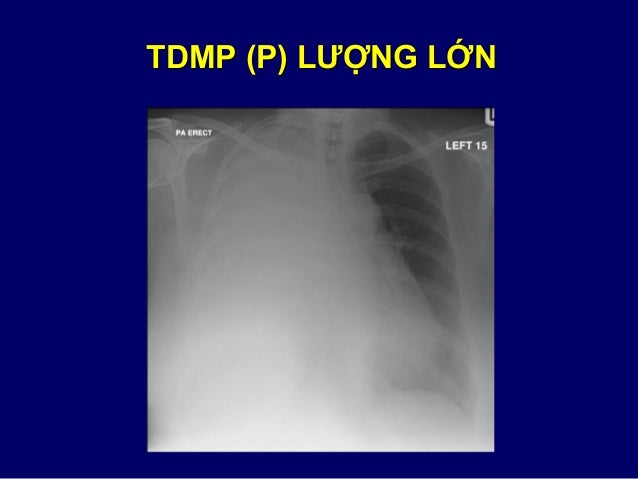

60. 60. 1. ĐÔNG ĐẶC – KÍNH MỜ CÁC NGUYÊN NHÂN  Nhiễm trùng phổi  Phù phổi do tim hay không do tim  Ung thư: phế quản – phế nang; lymphoma  Xuất huyết trong phổi

83. 83. TDMP (P) LƯỢNG LỚN

78. 78. 3. TRÀN DỊCH / DÀY MÀNG PHỔI  Dấu hiệu điển hình của TDMP: o Mờ vùng thấp (đáy phổi) o Đường cong lõm góc sườn hoành  Dấu hiệu gợi ý dày màng phổi ≠ TDMP: o Mất đường cong lõm  lên + giảm thể tích phổi o Mờ lên tận đỉnh phổi (cần ≠ TDMP khu trú) o Tổn thương ổn định so phim cũ  Cần phân biệt với xẹp, đông đặc phổi